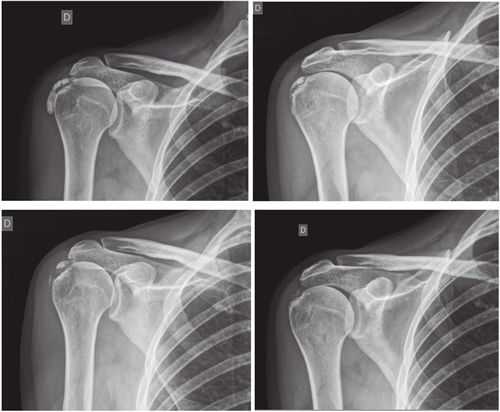

Resultados: Edad media: 54,6 años (n = 138); mujer (73,1 %; n = 101); proporción mujer/hombre 3: 1; tendón supraespinoso (94,6 %; n = 124); subescapular (5,4 %; n = 14); hombro izquierdo (55,1 %; n = 76), hombro derecho (44,9 %; n = 62); bilateral 1,4 % (n = 2); diestros 96,3 % (n = 133); antecedentes personales: tabaquismo (19,5 %; n = 27), diabetes (7,2 %; n = 10). El tiempo de enfermedad promedio fue de 6,08 meses. Dolor agudo-subagudo (menos de 3 meses) 47,1 %; (n = 65), dolor crónico (más de 3 meses) 52,9 % (n = 73). Tipo radiológico: formativo 75,3 % (n = 104), resortivo 24,7 % (n = 34). Número promedio de sesiones: 20. Complicaciones del tratamiento 2,8 % (n = 4): intolerancia/eritema/quemadura. Ocupación: administrativo 39,8 % (n = 55), trabajos manuales 60,2 % (n = 83). El dolor inicial EVA de 7,3 puntos disminuyó significativamente (p = 0,0000) después del tratamiento a 2,7. El tamaño promedio inicial de las calcificaciones fue de 10,7 mm y disminuyó significativamente (p = 0,0000) después del tratamiento a 3,8 mm. Cambio de calcificación: tasa de éxito/curación 55,7 % (n = 77), tasa de mejora 20,2 % (n = 28); tasa de fracaso del 23,9 % (n = 33). La limitación funcional disminuyó de un 10,8 % a un 2,1 %.

Results: Mean age 54.6 years (n = 138). Female (73.1 %; n = 101); female to male ratio 3:1. Supraspinatus tendon (94.6 %; n = 124), subscapularis (5.4 %; n=14); left shoulder (55.1 %; n = 76), right shoulder (44.9 %; n = 62). Bilateral 1.4 % (n = 2). Right handed 96.3 % (n = 133); Personal history: smoking (19.5 %; n = 27), diabetes (7.2 %; n = 10); disease time averaged 6.08 months; acute-subacute pain (less than 3 months) 47.1; (n = 65), chronic pain (greater than 3 months) 52.9 % (n = 73). Radiological type: formative 75.3 % (n = 104); resorptive 24.7 % (n = 34). Average number of sessions: 20.5. Treatment complications 2.8 % (n = 4): intolerance/erythema/burn. Occupation: administrative 39.8 % (n = 55), manual jobs 60.2 % (n = 83).